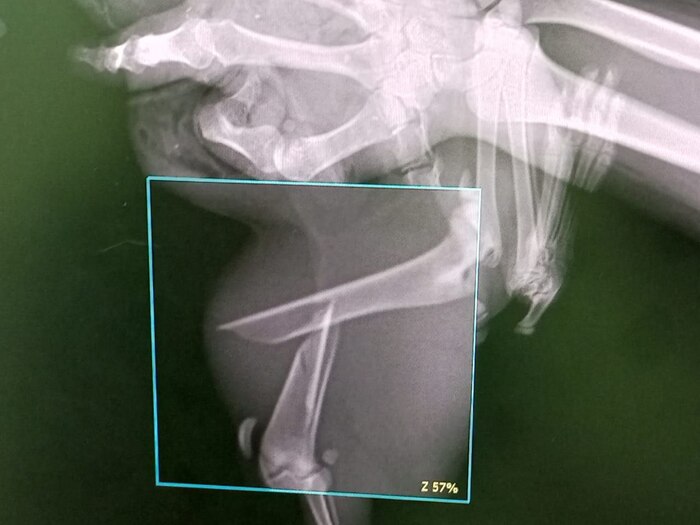

Уличного котёнка сбили самокатчики. Продолжение

Котенок Кроша жила в подвале, ее кормили и искали ей дом. Но 13 августа позвонили соседи и сказали, что котенка переехали нелюди на самокате, вероятно специально, так как загоняли котенка вдвоем. Свидетелем стал сторож бывшего института.

📌Итог: серьезный перелом лапы, содран скальп с челюсти, кожа не держится.

📌13 августа провели операцию на челюсти, подшили кожу.Оторванная от нижней челюсти кожа прижилась, швы сняли 👍

📌 🆘‼️‼️По сломанной лапе:

Её возьмут на операцию в Зоовет. Предварительно это будет установка спиц. Сегодня Кроша была на консультации у хирурга.

В среду готовы её взять на операцию. Шпак сказал , что операцию нужно делать срочно‼️ Иначе все срастётся не так! Он сказал будет некроз тканей так как перелом оскольчатый и следовательно там воспаление! Там есть осколки. Делать обязательно иначе она жить полноценно не сможет!

🙏🏻 Надеемся, что все сложится и ее возьмут на операцию 3 сентября.